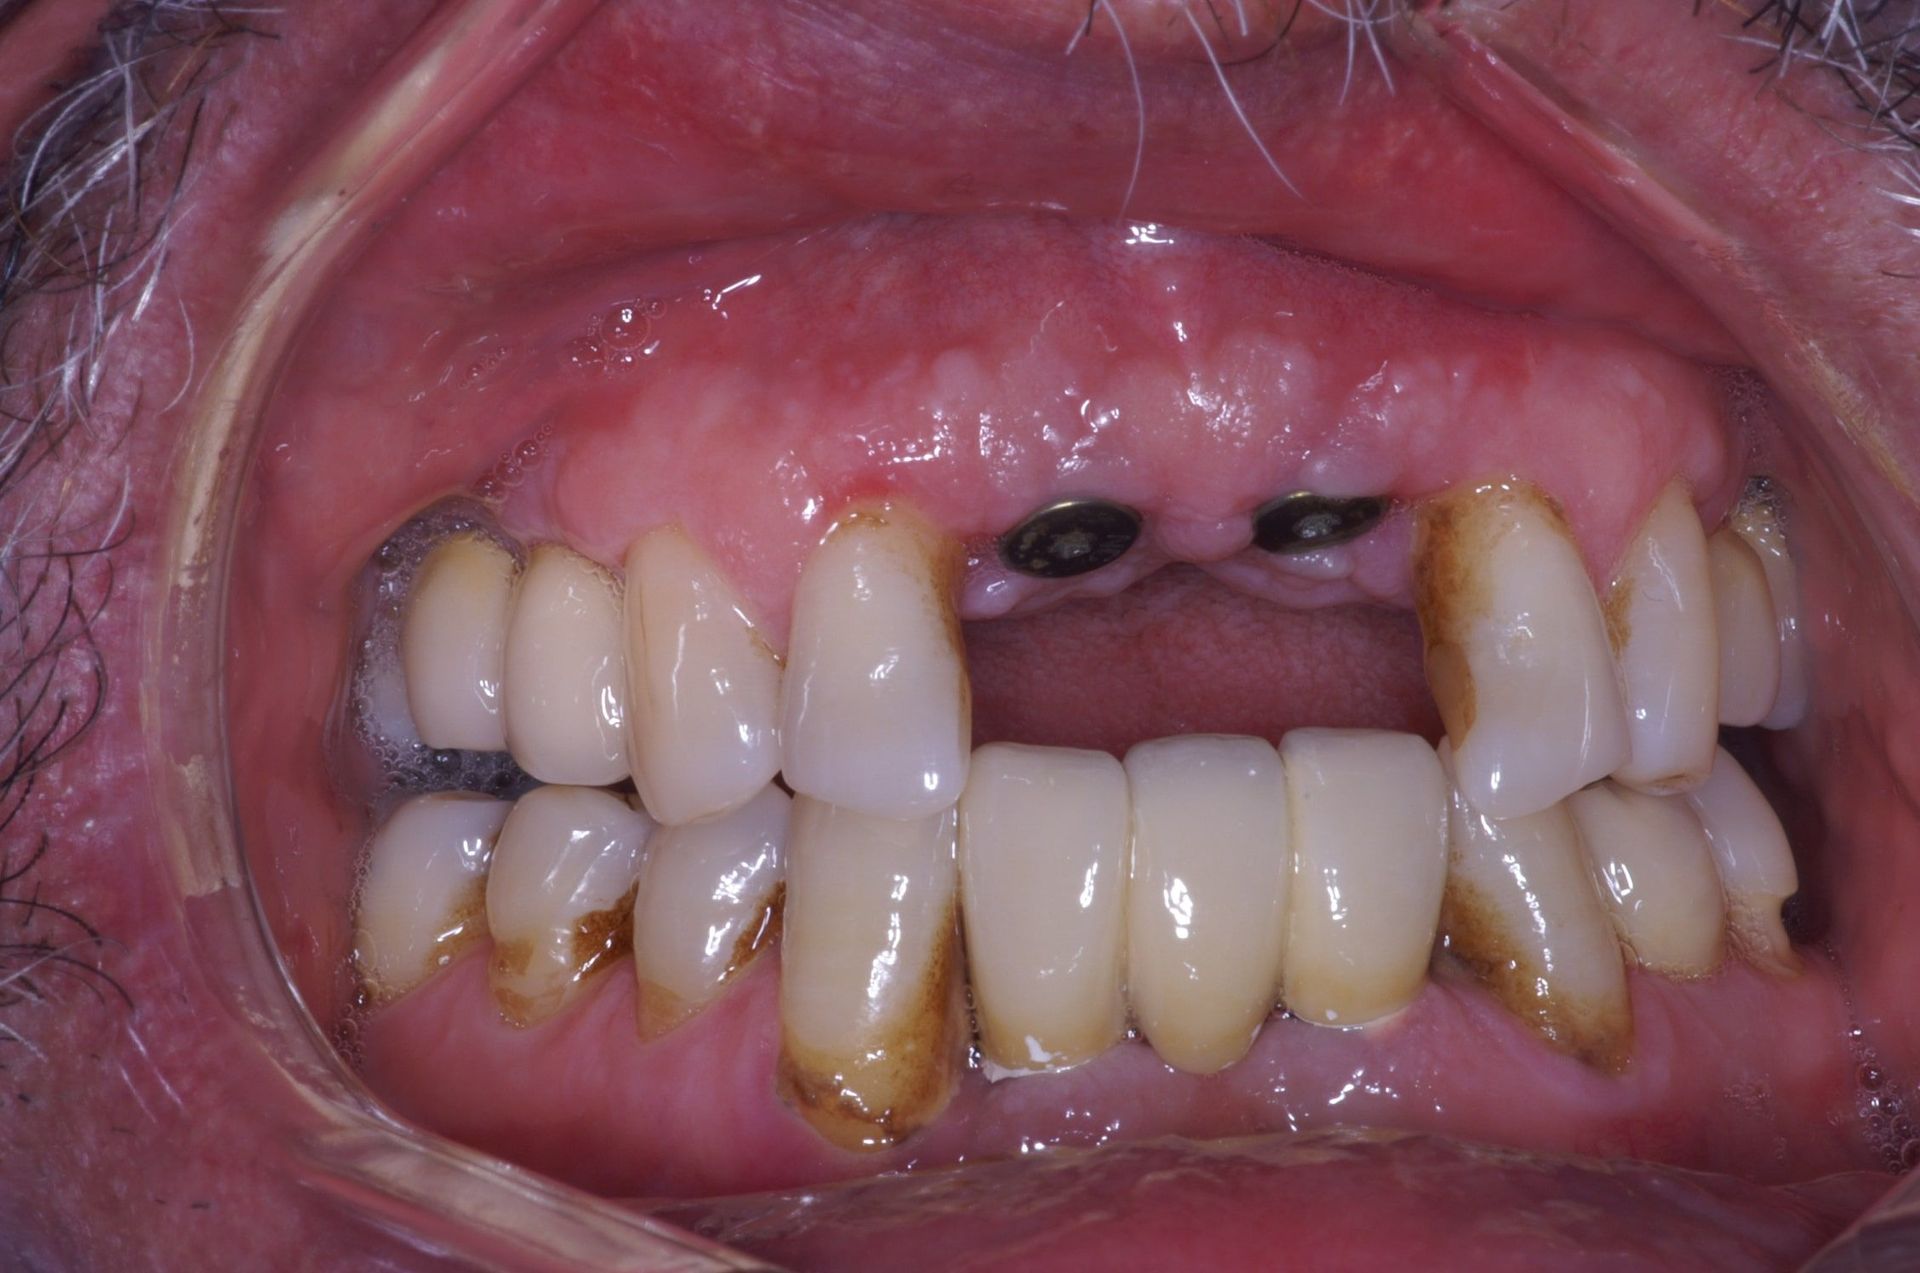

Avant et après implants